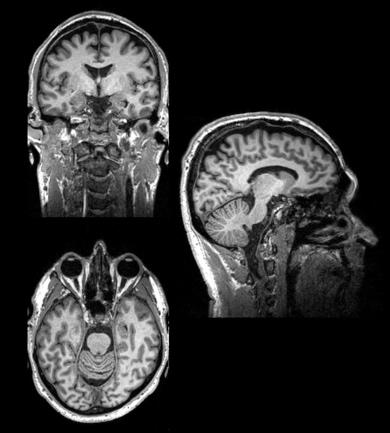

Fig. 2

The structure of a normal human brain revealed by MRI

MRI = magnetic resonance imaging – is used to analyse brain structures.

MRI is a technique that relies on having hugely powerful magnetic fields that are used to align molecules of water and other brain components that have paramagnetic properties. The alignment of these molecules is perturbed by pulsing radio waves from electromagnetic coils [head coils] into the brain, and measuring how they return to their prior alignment. This can give a number of measures of brain structure based on the water or fat content of different regions [often called structural imaging] fig 2. This is used to help make diagnoses in neurological and psychiatric disorders eg stroke and dementia. It is also a vital tool in helping identify the brain regions that are identified in other forms of scanning such as fMRI and PET. Depending on the magnet strength [stronger is better] and duration of scanning [longer is better] resolutions of millimetre scale can be obtained – so allowing analysis of specific sub fields of brain regions eg hippocampus.